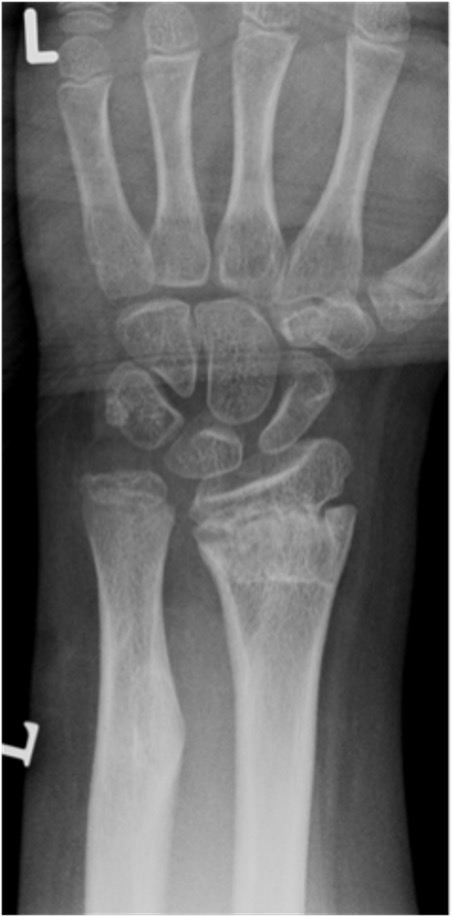

Mercer Rang Remodelling Rules

Best if

- young age (won't remodel much if > 11 years)

- short distance from fracture to physis

- direction of angulation in plane of motion of joint

Won't correct rotation

Rang distal radius remodelling

- < 5 - 25-35°

- 4 - 9 - 20-25

- 10-12 - < 15°